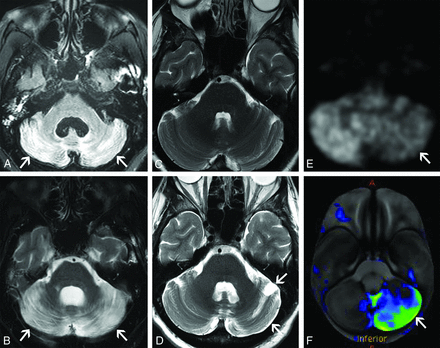

Imaging findings of PCD depend on the phase of the syndrome. In the acute phase, increased T2 signal within the cerebellar hemispheres can be seen (Fig 4A, -B). At this stage, the differential diagnosis includes infectious or inflammatory cerebellitis. In the chronic phase, T2 hyperintensity improves, and cerebellar FDG-PET hypometabolism, atrophy, or both may be seen (Fig 4C–F). The differential diagnosis for chronic PCD includes alcoholic degeneration, neurodegenerative disorders such as multiple system atrophy (cerebellar subtype), and sequelae from infectious/inflammatory cerebellitis. Careful attention to patient history, such as prior alcohol use disorder or cerebellar infection, is most important in distinguishing these entities.

Subacute paraneoplastic cerebellar ataxia (A and B). A 58-year-old woman presented with headaches, vertigo, and ataxia that had progressed over a period of weeks. CSF analysis showed a high titer of PCA-1 autoantibodies. After additional work-up, she was found to have metastatic breast adenocarcinoma. Axial FLAIR (A) and T2-weighted (B) images of the brain show marked T2 hyperintensity diffusely involving both cerebellar hemispheres (A and B, arrows). No enhancement was seen on postgadolinium images (not shown). The patient was diagnosed with paraneoplastic cerebellar degeneration. She had mild improvement in her neurologic symptoms with high-dose corticosteroids but remained wheelchair dependent. Chronic paraneoplastic cerebellar ataxia (C–F). A 56-year-old woman presented with progressive ataxia over a period of several months. Paraneoplastic serum antibody panel revealed anti-G-AchR (ganglionic acetylcholine receptor) antibodies, and CSF analysis revealed increased protein concentration and high IgG levels. Initial axial T2-weighted image of the brain (C) and subsequent axial T2-weighted image from an examination several months later (D) show interval development of mild left cerebellar atrophy (D, arrows). FDG-PET axial source image of the brain (E) and processed surface rendering of the brain compared with age-matched control participants (F) show marked hypometabolism within the left cerebellar hemisphere (E and F, arrows). No cerebral lesion was present to suggest crossed cerebellar diaschisis. Review of prior records noted an FDG-avid thyroid lesion found to be a follicular neoplasm on resection. She was diagnosed with paraneoplastic cerebellar degeneration with chronic atrophic features. Her symptoms have been stable on cyclophosphamide with pulsed corticosteroids.